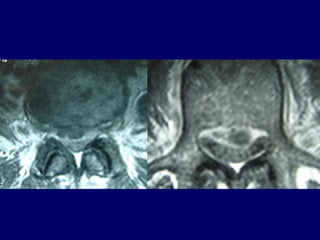

Intramedullar

abscess